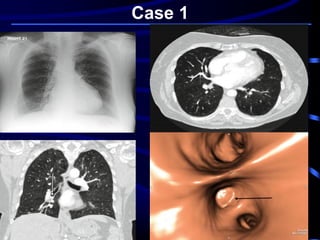

◙ An 81-year-old woman presented to A/E with

a history of recent onset of shortness of

breath. This had come on during dinner the

previous evening and had not resolved.

◙ She had asthma as a child, and cardiac

bypass 5 years ago. Blood tests indicated a

negative troponin and normal D -dimer.

◙ A chest X ray was done followed by CT

Case 1

What is the MOST LIKELY

diagnosis?

A. Left sided heart failure

B. Bronchial asthma.

C. FB inhalation.

D. Bronchogenic carcinoma.

E. Pulmonary embolism.